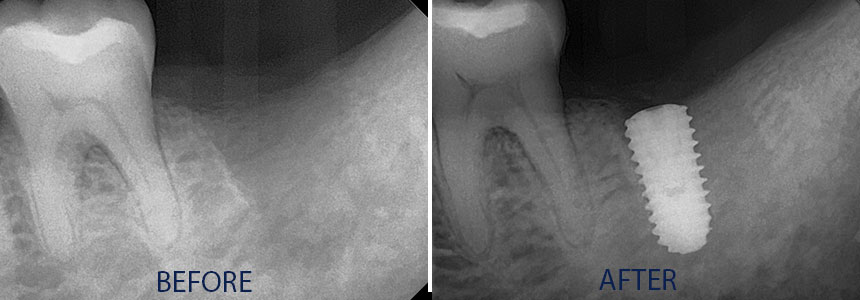

An implant is a synthetic tooth root in the shape of a post that is surgically placed into the jawbone. The “root” is usually made of titanium: the same material used in many replacement hips and knees, and a metal that is well-suited to pairing with human bone. A replacement tooth is then fixed to the post. The tooth can be either permanently attached or removable. Permanent teeth are more stable and feel more like natural teeth.